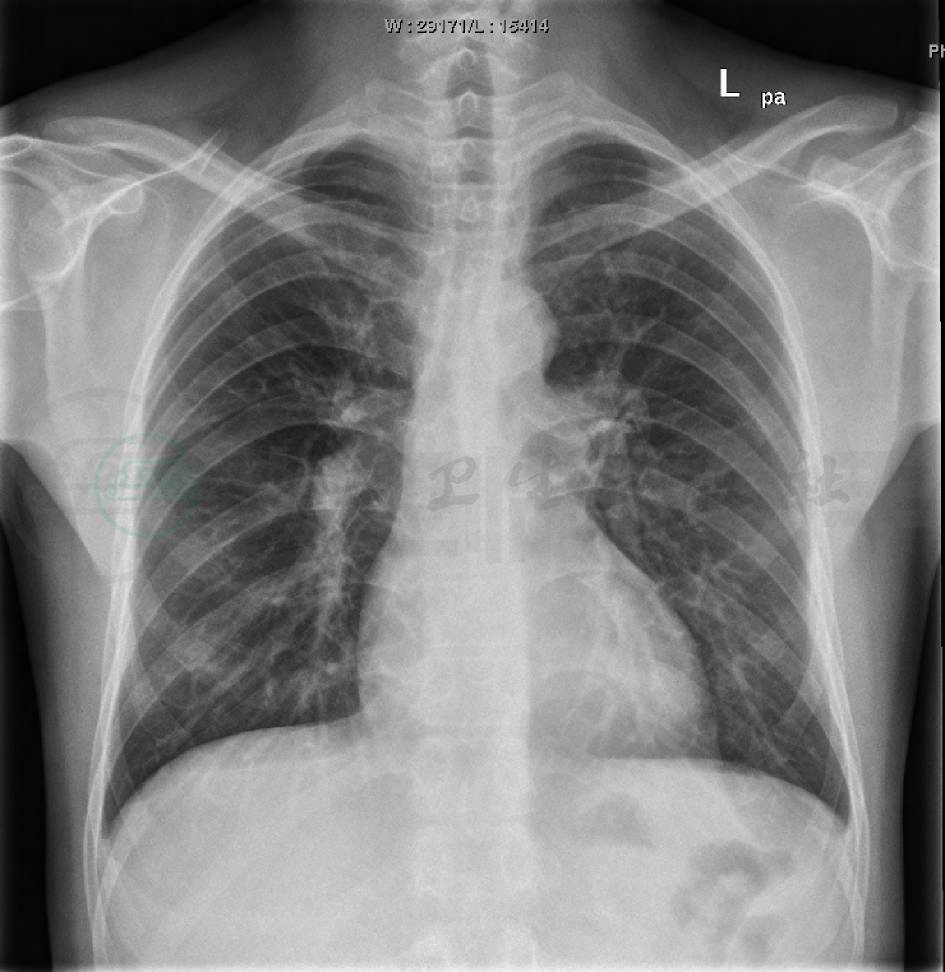

心脏彩超提示右心房46mm,右心室45mm,肺动脉内径33mm,先天性心脏病,室间隔缺损(膜周部),重度肺动脉高压110mmHg,心室水平双向分流,以右向左分流为主。胸片和心电图检查见图1~图3。

图1 入院胸片

心影增大,右下肺感染